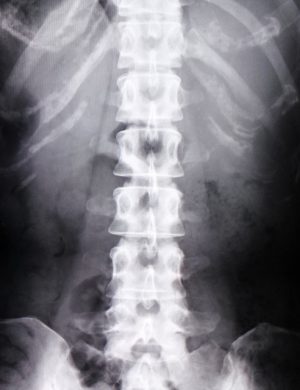

①(レントゲン検査など)画像検査にてあきらかな異常が見らる(骨や椎間板自体に変性が見られる)

「特異的腰痛」というものと

(一般的に病院などではこの状態を,椎間板ヘルニアや脊柱管狭窄症と診断しています)

②画像上は異常が見られない(レントゲン上は正常と言われる)「非特異的腰痛」

この2つに分類されます。